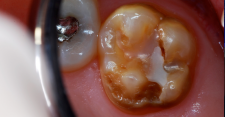

A distolingual cusp was destroyed by caries.

Figure 6

The same boy pictured in Case 1, in another dentistry office, had occlusal-lingual resin-based composite restoration of his malformed maxillary right first molar about 18 months previously. The bonded repair had been completed expertly and was holding up well. However, the boy developed a new caries lesion involving the distolingual cusp (Figure 6). After local infiltration anesthetic injection, a cotton roll was placed in the mucobuccal fold to absorb saliva from the parotid duct in the cheek.

The occlusal-distolingual tooth preparation was completed, and a stainless steel orthodontic band was pressed into place to serve as a matrix (Figure 7). After two 60-second applications of a 5% glutaraldehyde/HEMA desensitizing solution, a self-etching bonding agent was painted on the enamel surfaces. An RMGI bioactive ionic resin-based composite was then injected in two portions (Figure 8), with 10-second light beam exposure between the injections. After the material was injected to overfill, the light beam was applied once more, for 20 seconds (Figure 9). The restoration was then trimmed and finished in the usual manner using large, round diamond burs at slow speed and diamond finishing burs on the axial surfaces (Figure 10). The self-etching bonding agent was then applied as a final glaze, and occlusal contacts were adjusted using articulating paper as a guide.